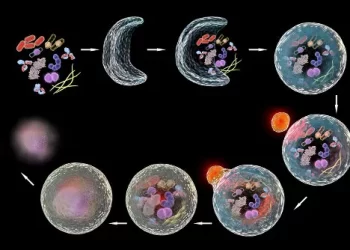

Autofagia: o processo natural de renovação celular

Sentir fome ativa mais do que o apetite: desencadeia um processo natural chamado autofagia, pelo qual o corpo “recicla” suas...